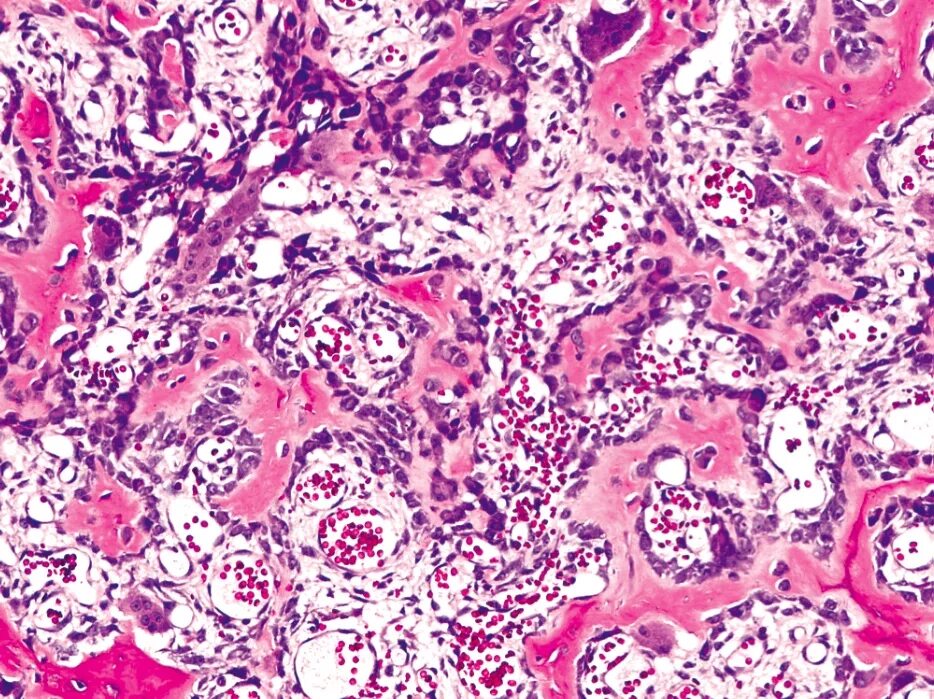

Патанат